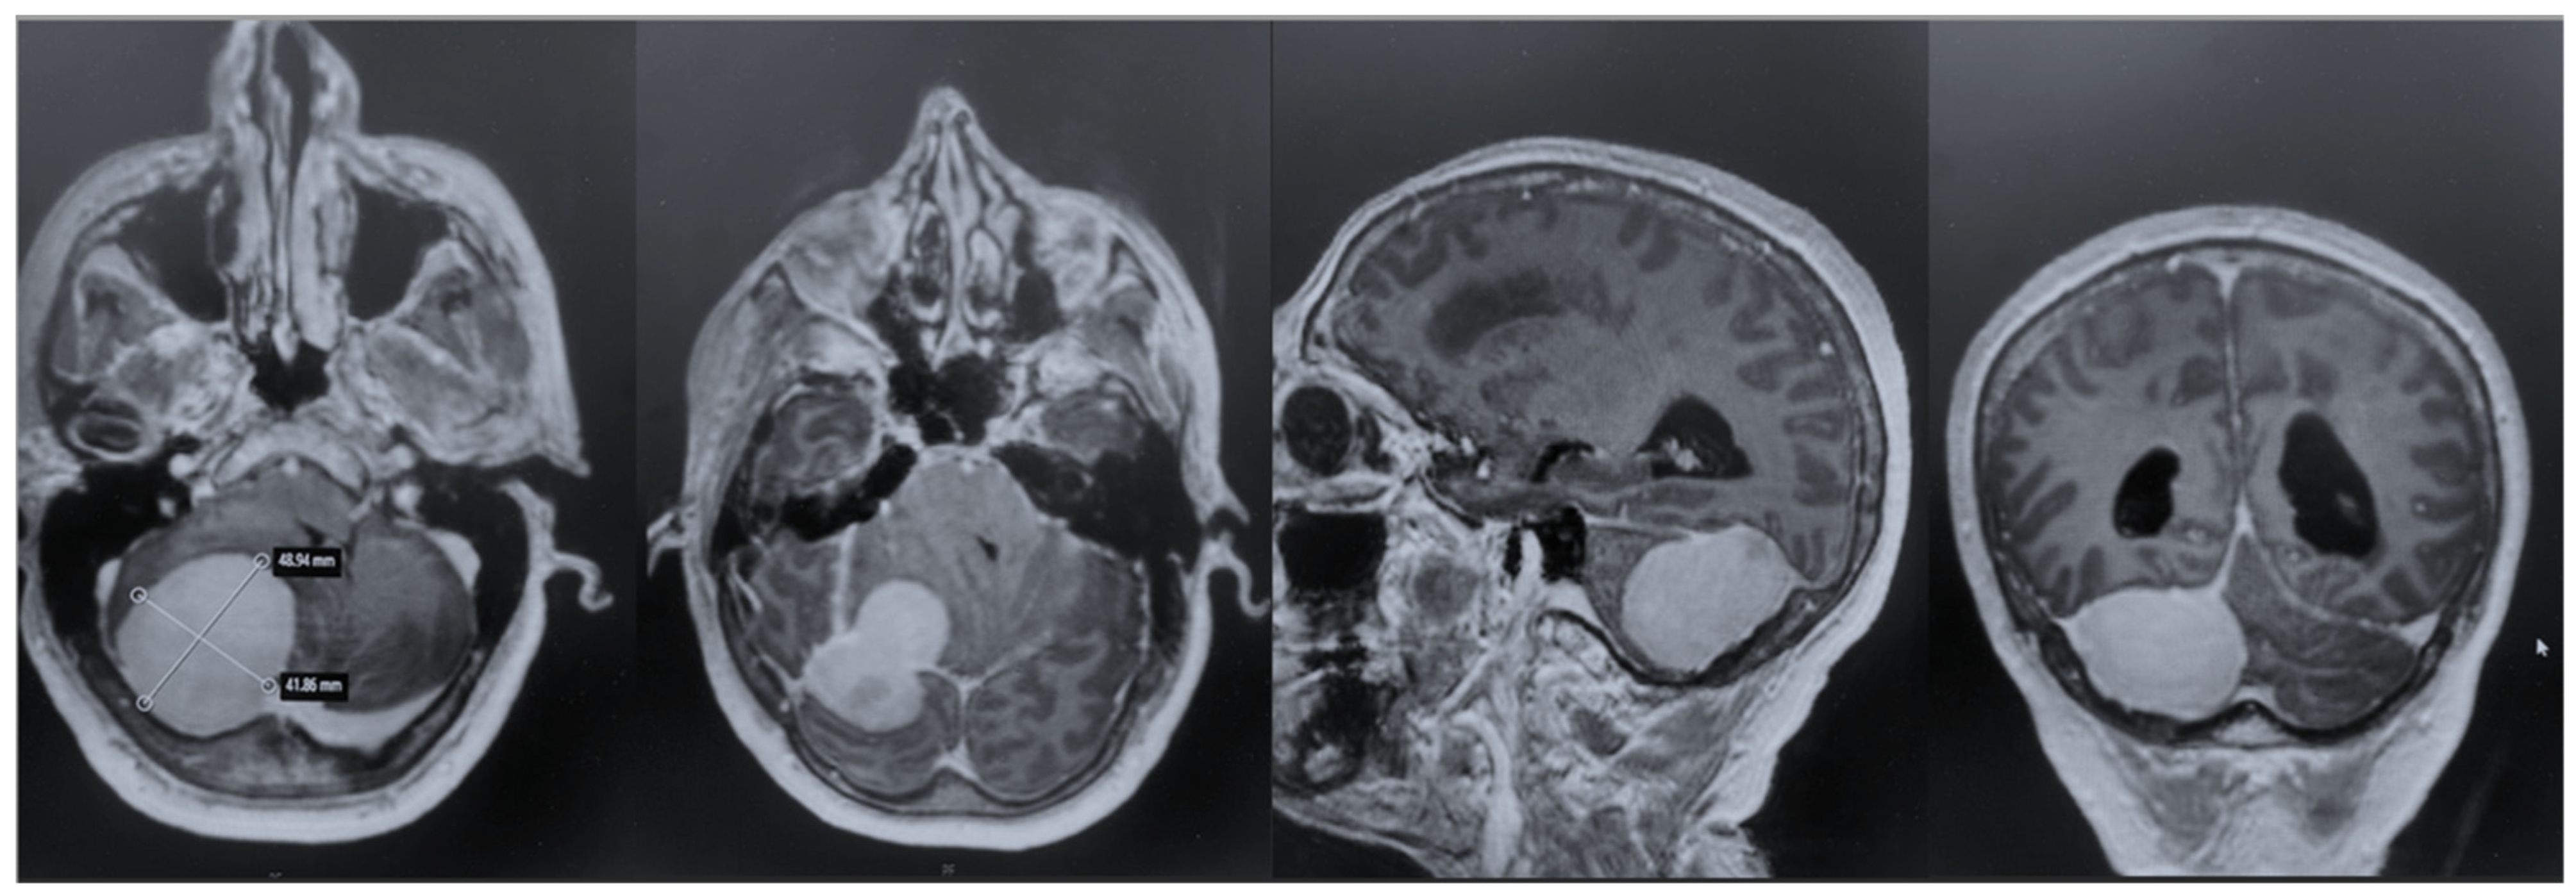

After admission, the patient underwent a cerebral MRI, which showed a huge extra-axial lesion in the posterior cranial fossa (5 × 4.4 × 4.3 cm). The lesion demonstrated low SI on T1 and intermediate SI on T2 and avidly enhancing post-Gad administration. The mass showed no restriction on DWI. The mass was broad-based on the right tentorium cerebelli with a discrete supratentorial extension, compressing the adjacent right cerebellar hemisphere, the cerebellar peduncle, the brainstem, the IV ventricle, and the right occipital lobe. A characteristic dural tail sign was demonstrated on post-Gad sequences (Figure 1).

Figure 1. Preoperative MRI + C: a posterior fossa extra-axial mass was demonstrated, showing a low SI on T1 and intermediate SI on T2, which avidly enhanced post-Gad administration. The mass was broad-based on the right tentorium cerebelli with a discrete supratentorial extension, thus compressing the adjacent right cerebellar hemisphere, the brainstem, the IV ventricle, and the right occipital lobe.